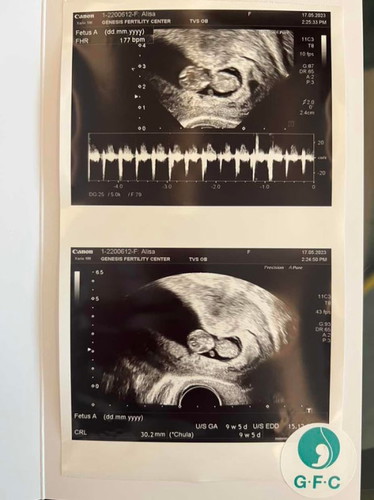

น้อง 9 วีค 5 วัน

นับวันรอไป Ultrasound ได้เห็นหนูแล้ว แขนขา มือเท้ามาแล้ว ดุ๊กดิ๊กโชว์แม่ด้วย ❤️

VIP Parentsนับวันรอไป Ultrasound ได้เห็นหนูแล้ว แขนขา มือเท้ามาแล้ว ดุ๊กดิ๊กโชว์แม่ด้วย ❤️